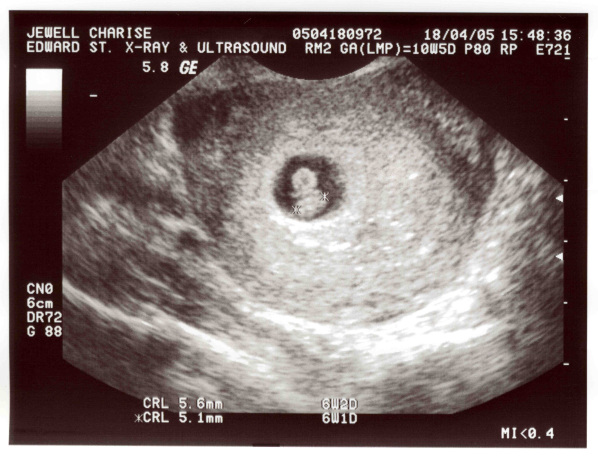

Losing the dream: pregnancy loss and how to cope

Article about how to work through the grief caused by a miscarriage or pregnancy loss. Published online by CRUNCH compass. https://chaell.wordpress.com/2013/10/18/losing-the-dream/